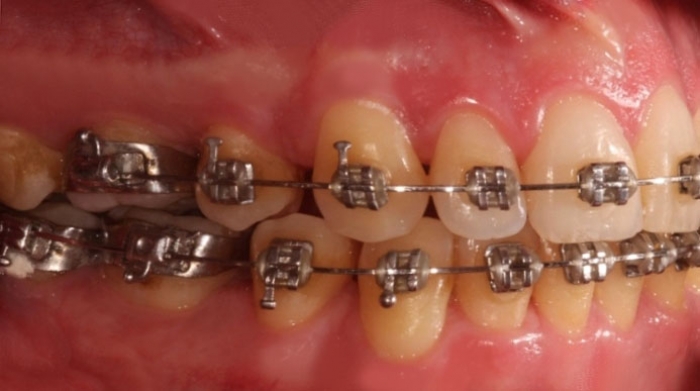

Mordida após a cirurgia